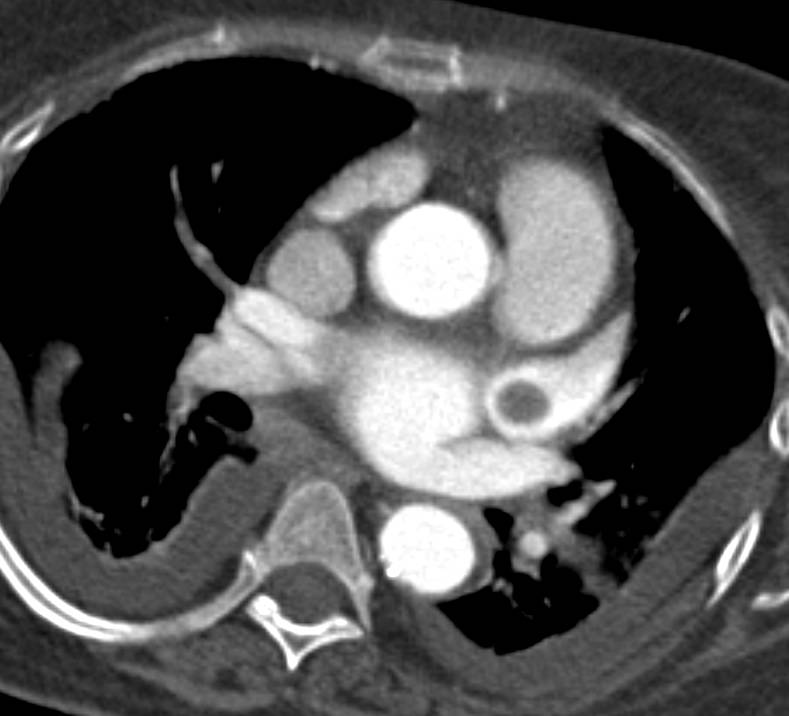

CCTA: Co-Dominant Circulation